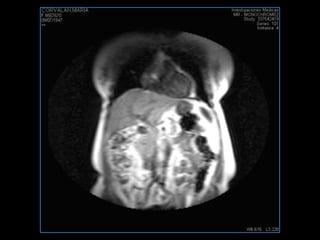

PROTOCOLO abdomen COR T2, AXIAL supresion grasa AX T1 +SAG T2  CON   GADOLINIO :  COR T1+AX T1(DIN) SAT: NO  FASE: RL THK: 6MM  COIL:  GAP: (FACTOR 1.4) 2MM FOV: 40 CM NEX:2 SINCRONIZACION RESPIRATORIA EN 3 O 4 CICLOS ALE

resonancia de abdomen